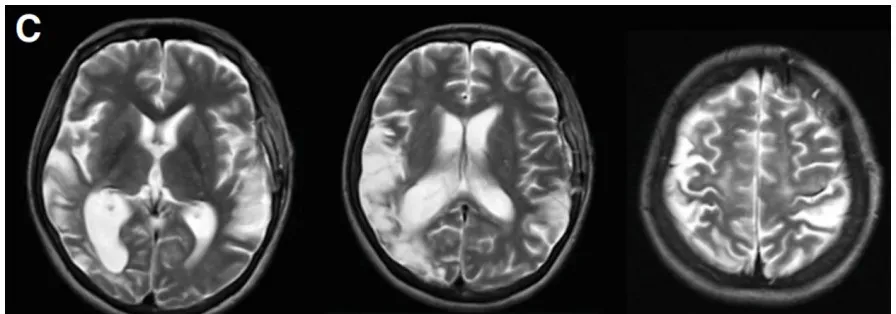

图3C:术后23天MR复查显示未出现新的缺血性或出血性病变,恢复良好